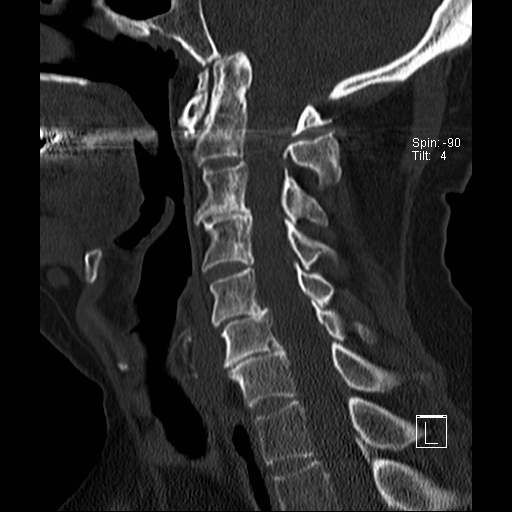

Lồng nền sọ

Lồng nền sọ, còn gọi là sụt lún sọ não hay ấn nền sọ, xảy ra ở 5-10% bệnh nhân viêm khớp dạng thấp cột sống cổ.

Trong lồng nền sọ, mỏm răng sa vào lỗ chẩm làm thu hẹp không gian dành cho tủy sống.

Biểu hiện lâm sàng đa dạng, từ đau đầu mạn tính, hạn chế vận động cổ đến suy giảm thần kinh cấp tính (chèn ép tủy sống và thân não, có thể dẫn đến liệt hoặc thậm chí tử vong nếu cổ bị di chuyển ở một số tư thế nhất định).

Hình ảnh

Cuộn xem các lát cắt CT.

Có hình ảnh di chuyển lên trên của mỏm răng vào lỗ chẩm.